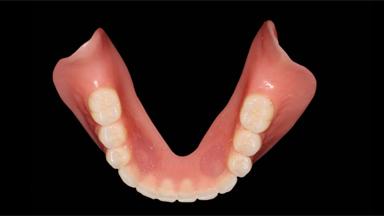

Maxillary Complete Denture and Mandibular Overdenture on Two Implants with Universal Design

A 78-year-old female patient was referred by the Department of Neurosurgery to the Department of Biomaterials and Prosthodontics of Kyung Hee University Dental Hospital, Gangdong, Seoul, South Korea. The patient was suffering from facial nerve palsy due to an ischemic stroke that had left parts of her eye, chin, lip, tongue, and extremity paralyzed. She had been wearing maxillary and mandibular complete dentures for 10 years, but after the stroke they were not suitable anymore as her mandibular denture became dislodged during function. In our aging society, dentures for the disabled and elderly are crucial in terms of patient satisfaction and health-related quality of life. Patients suffer from chronic and severe disorders, and elderly/disabled patients need special dental care. The provision of dentures using a minimally invasive treatment approach and a universal design are important issues (Leesungbok 2004).